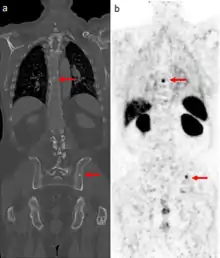

A gallium scan is a type of nuclear medicine test that uses either a gallium-67 (67Ga) or gallium-68 (68Ga) radiopharmaceutical to obtain images of a specific type of tissue, or disease state of tissue. Gallium salts like gallium citrate and gallium nitrate may be used. The form of salt is not important, since it is the freely dissolved gallium ion Ga3+ which is active.[1] Both 67Ga and 68Ga salts have similar uptake mechanisms.[2] Gallium can also be used in other forms, for example 68Ga-PSMA is used for cancer imaging. The gamma emission of gallium-67 is imaged by a gamma camera, while the positron emission of gallium-68 is imaged by positron emission tomography (PET).

Gallium salts are taken up by tumors, inflammation, and both acute and chronic infection,[3][4] allowing these pathological processes to be imaged. Gallium is particularly useful in imaging osteomyelitis that involves the spine, and in imaging older and chronic infections that may be the cause of a fever of unknown origin.[5][6]

In the past, the gallium scan was the gold standard for lymphoma staging, until it was replaced by positron emission tomography (PET) using fludeoxyglucose (FDG).[9][10] Gallium imaging is still used to image inflammation and chronic infections, and it still sometimes locates unsuspected tumors as it is taken up by many kinds of cancer cells in amounts that exceed those of normal tissues. Thus, an increased uptake of gallium-67 may indicate a new or old infection, an inflammatory focus from any cause, or a cancerous tumor.

The main (67Ga) technique uses scintigraphy to produce two-dimensional images. After the tracer has been injected, images are typically taken by a gamma camera at 24, 48, and in some cases, 72, and 96 hours later.[23][24] Each set of images takes 30–60 minutes, depending on the size of the area being imaged. The resulting image will have bright areas that collected large amounts of tracer, because inflammation is present or rapid cell division is occurring. Single-photon emission computed tomography (SPECT) images may also be acquired. In some imaging centers, SPECT images may be combined with computed tomography (CT) scan using either fusion software or SPECT/CT hybrid cameras to superimpose both physiological image-information from the gallium scan, and anatomical information from the CT scan.